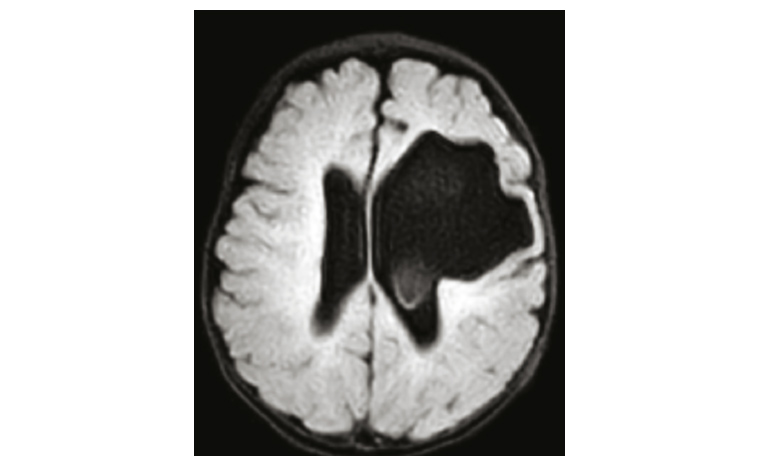

Due to the clinical findings, which did not fit with a typical congenital torticollis of muscular origin, a head ultrasound was arranged, which showed a large area of missing parenchyma in continuity with the body of the left lateral ventricle with dilated lateral ventricles. Magnetic resonance imaging of the brain was arranged to further delineate, which showed a large left frontal lobe porencephalic cyst communicating with the left lateral ventricle (Figure 1). There was also evidence of previous intraventricular haemorrhage with associated hydrocephalus and minor mass effect.

Figure 1. Magnetic resonance imaging of the brain, T2-weighted fast fluid-attenuated inversion recovery, axial view. The image shows a large porencephalic cyst communicating with the left lateral ventricle. Taken from the patient’s record with consent.